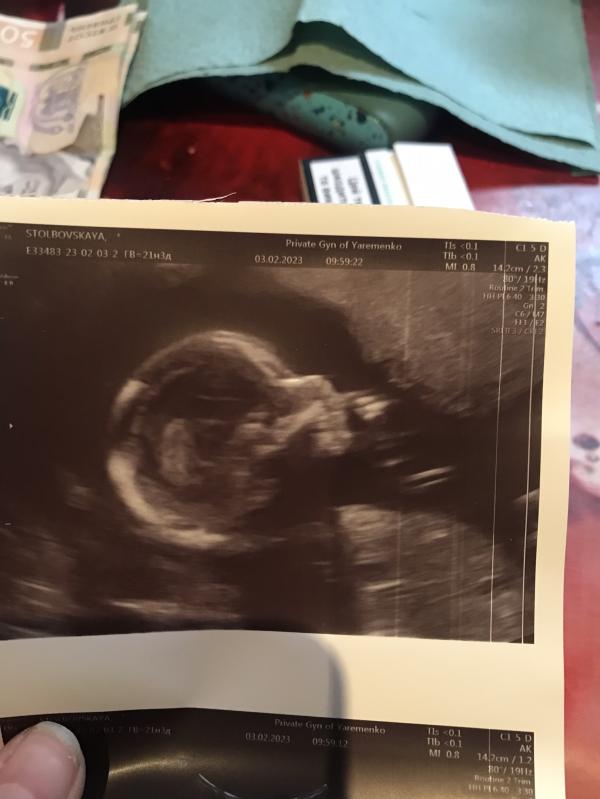

Всем привет:) были сегодня на 2 скрининге, у Ярьоменко. Осталась довольна врачом, хотели видео 3д на память, но ребёнок не удобно лежал:) в другой раз сказал сделаем, на узи сердца нужно идти к нему в 20-х числах марта. По скринингу все ок, отклонений никаких нет:))) Подтвердил пол, будет малышка, доченька, муж очень рад, сидел со мной и тоже смотрел:) Врач сделал фото как малая руку в рот засовывала, открывала рот:)

Яременко - врач супер! Все скрининги делала у него, и пол нам определил уже на 13 недели.

Нет, я первый делала по месту где стала на учёт, в 5 роддоме возле ЮЖД. Второй уже у него, врач хороший, внятный, сдержанный, ничего лишнего не сказал, все по факту,врач высшей категории, я даже так скажу, моя мама была у него со мной, он меня на узи видел, подтвердил маме что у неё будет девочка) Очень советую Ярьоменко) первый раз мне пол сказали на 15 неделе, я не сдержалась и пошла узнавать к Ткачеву в Доктор Алекс)